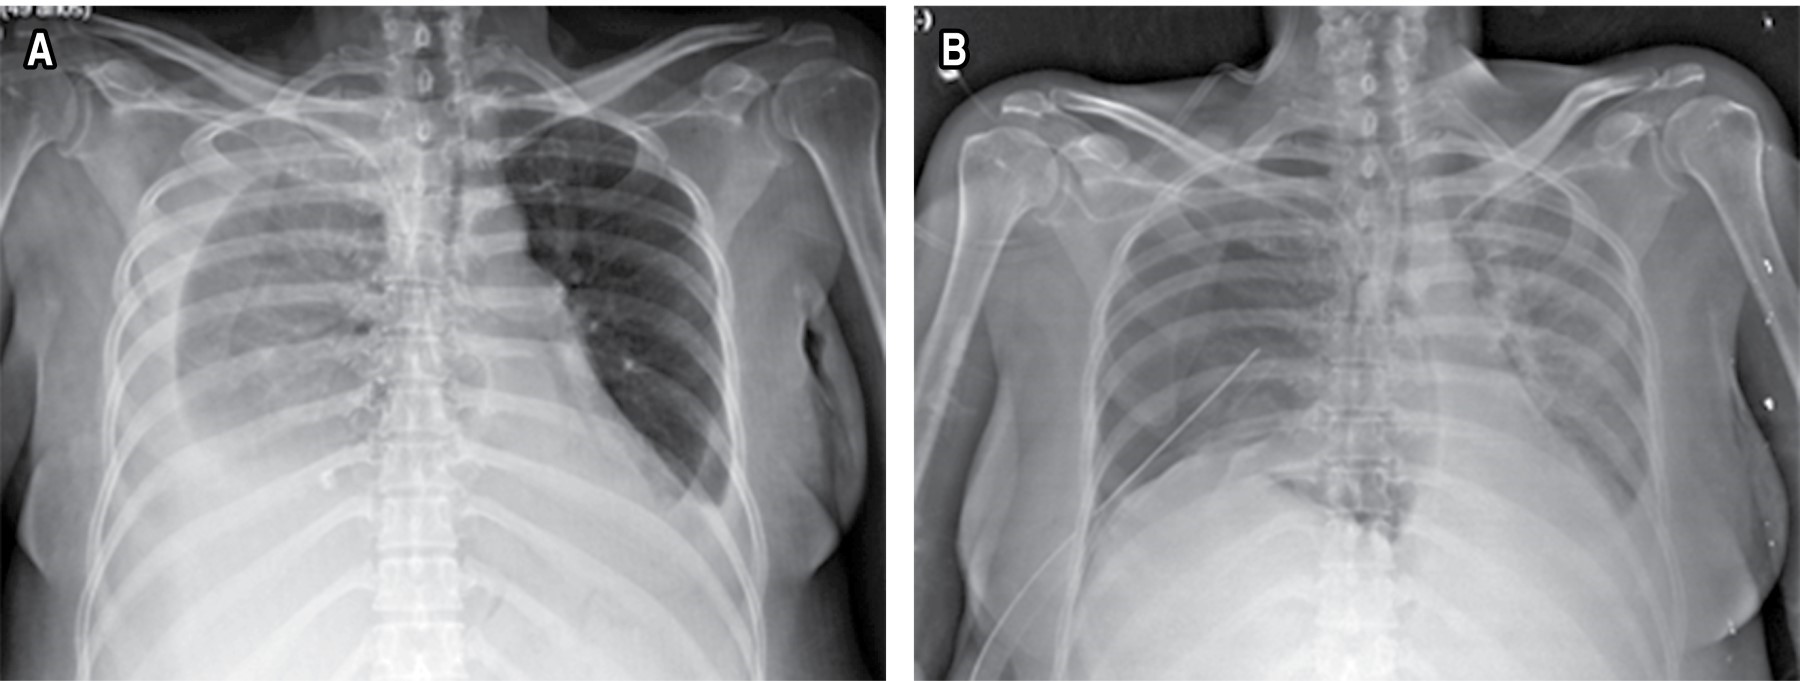

Es enviada a nuestro servicio el 27-10-19, recibiéndola con oximetría de 85% y anasarca, se realiza telerradiografía de tórax a su ingreso que evidencia derrame pleural derecho de 40% aproximadamente, colocándose sello de agua en sexto espacio intercostal con línea media axilar derecha y verificando su colocación con una placa de tórax de control que asegura la colocación de la sonda, planteándose laparotomía exploradora al 29-10-19 (Figura 3).